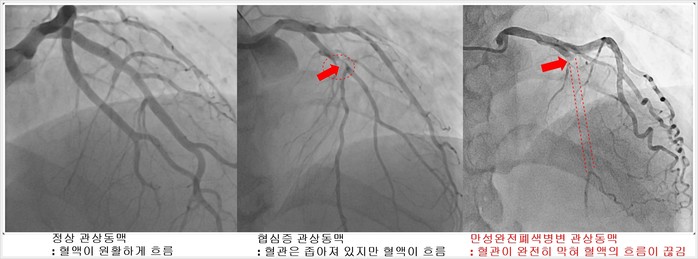

| ▲1. 정상 관상동맥 - 혈액이 원활하게 흐름 2. 협심증 관상동맥 – 혈관은 좁아져 있지만 혈액이 흐름 3. 만성완전폐색병변 관상동맥 – 혈관이 완전히 막혀 혈액의 흐름이 끊김 <이미지 서울아산병원 제공> |

만성완전폐색병변은 시간이 지나면서 협심증 증세가 악화되고 심부전으로 진행될 수 있는데, 대부분의 환자는 주위 다른 혈관에서 혈류 공급을 받기 때문에 심장기능이 정상이고 증상도 거의 없거나 경미하다. 관상동맥의 일부가 막히는 협심증이나 심장혈관 안의 죽상반이 터지면서 갑자기 막혀 심장근육의 괴사를 일으키는 심근경색증에서는 막힌 혈관을 뚫는 스텐트 시술이 기본 치료법으로 자리매김하고 있다.

관상동맥 만성완전폐색병변에서도 스텐트 치료법은 기구나 재료의 발전과 시술 의사들의 숙련도가 높아지면서 성공률과 합병증 모두 좋아지고 있지만, 아직까지는 단순 협심증에 비해 시술 난이도가 높고 합병증 발생의 위험과 비용도 높다.